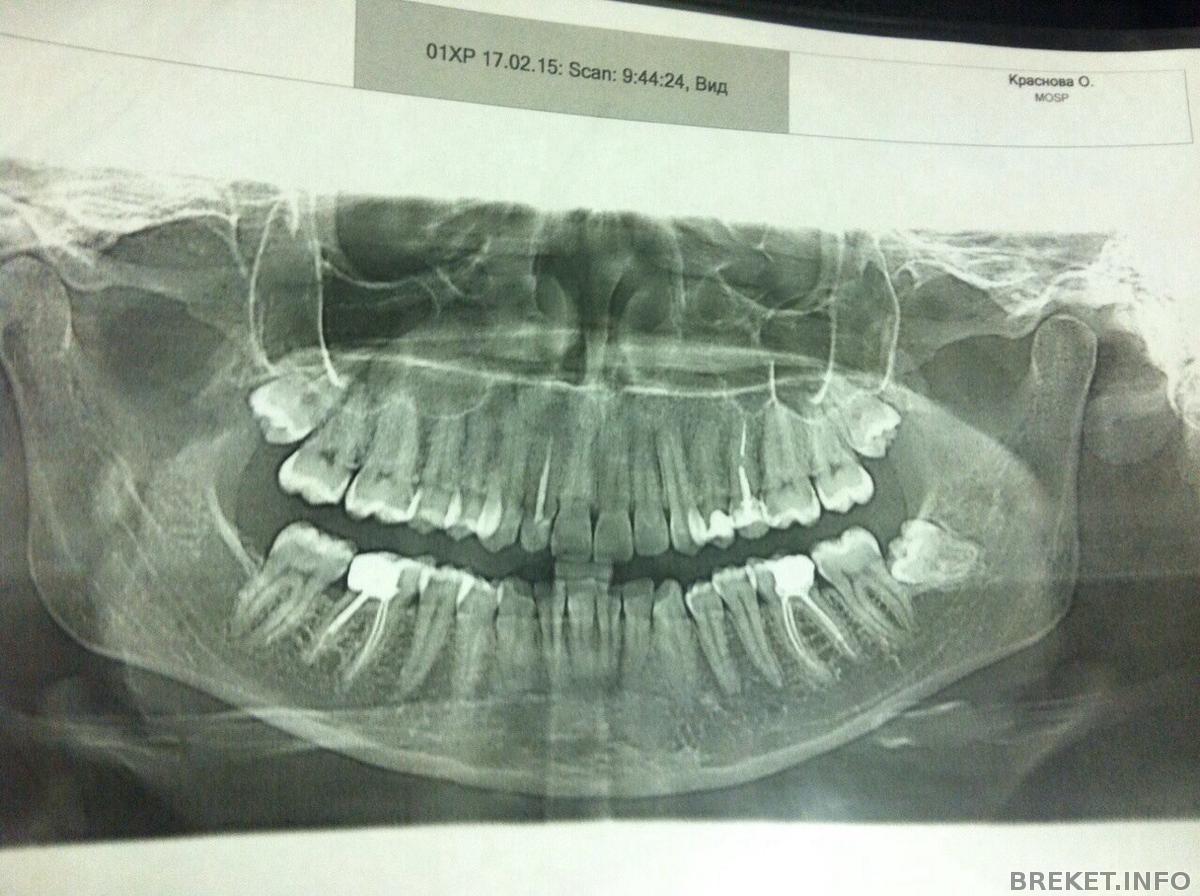

Вообщем, спустя год я вернулась к вопросу установки, вплотную и серьезно, удалось скопить часть денег, чтобы приступить к выполнению моей давней мечты. Выбрала место, врача. Пришла на консультацию и естественно направили первым делом на снимок, смотреть есть ли у меня зубы мудрости в зачатках. Оказалось у меня их целых 3....ортодонт говорит нужно удалить все, а потом ставить систему. Боюсь удалять до жути

у меня 2 вверху и 1 внизу. Скажите, обязательно сразу 3 до установки удалять или можно внизу например, через какое то время после установки брекетов удалить? Просто боюсь уже после удаления первого забью на все и брошу ![]()

А вот, собственно, и я в рентгене)))))

А где у вас на НЧ зуб мудрости с левой стороны?Его там от природы не было?

Логарифм Брекета, его и не было)) от природы))) рада была бы если б и остальных не было, ну или один хотя бы)))